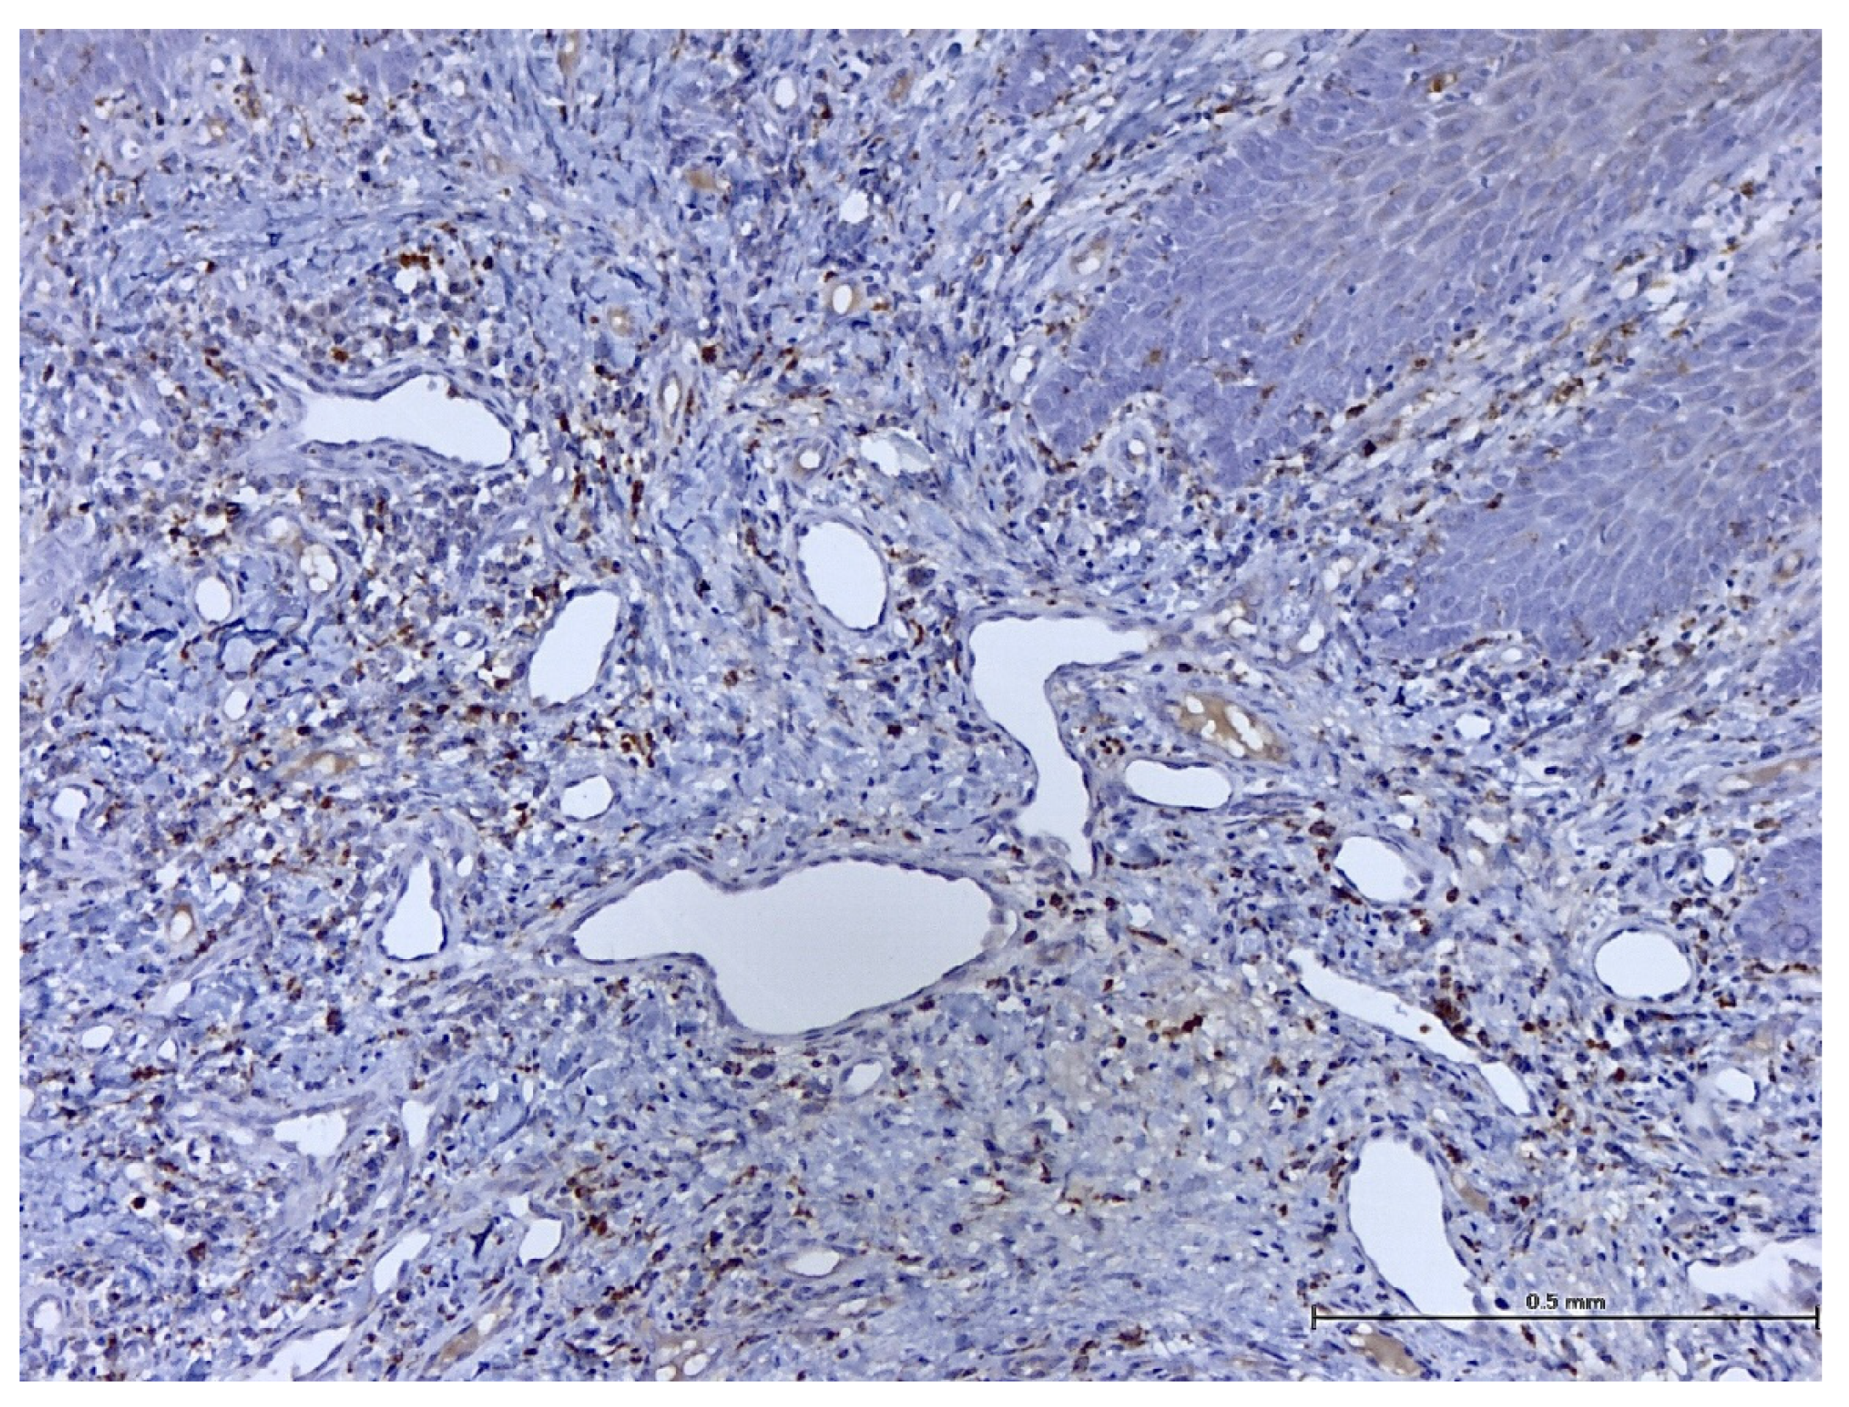

3. Results